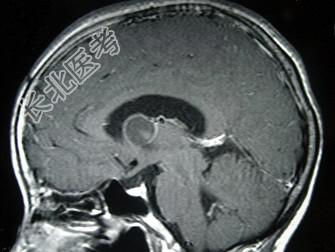

- 单项选择题女,29岁, 头痛、头昏10年,伴记忆力下降, 根据所提供图像,最可能的诊断是 ( )

A、胶样囊肿

B、蛛网膜囊肿

C、胶质瘤

D、室管膜瘤

E、表皮样囊肿